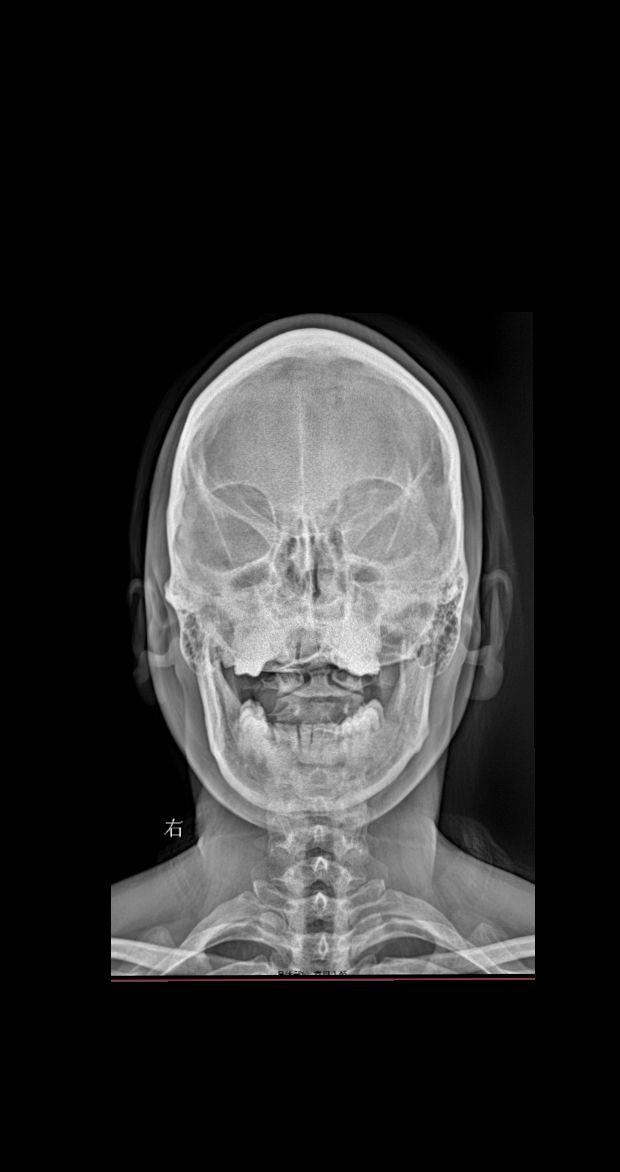

颈部疼痛 头晕 就诊